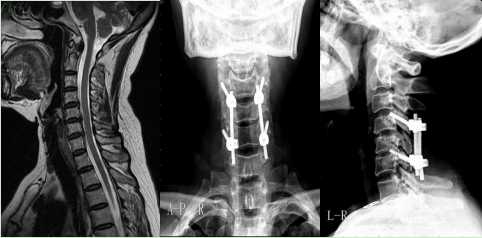

1.頸椎管狹窄后路椎管擴(kuò)大減壓側(cè)塊螺釘內(nèi)固定